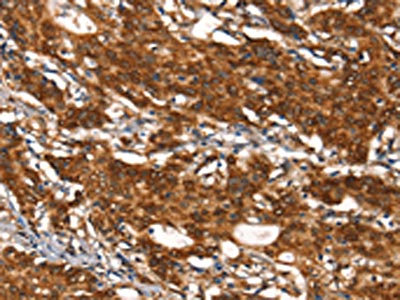

The image on the left is immunohistochemistry of paraffin-embedded Human gastic cancer tissue using CSB-PA051152(CYP2D6 Antibody) at dilution 1/30, on the right is treated with synthetic peptide. (Original magnification: ×200)